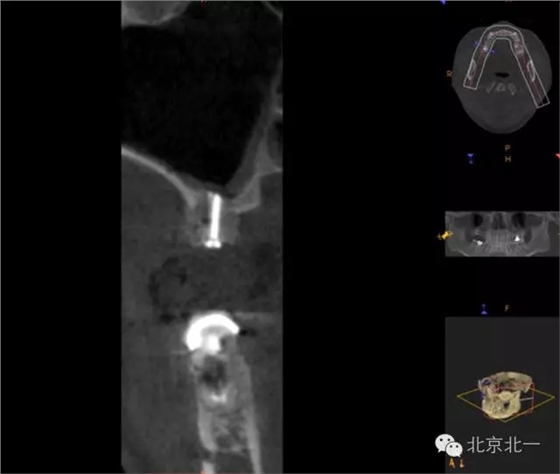

圖十八:手術前CBCT

圖十九:手術后當天CBCT

圖二十-二十二:ONLAY植骨半年后